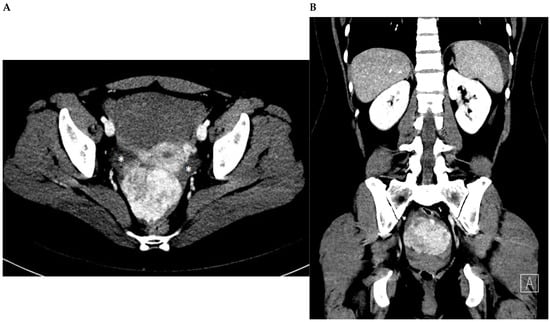

Figure 1. A woman without comorbidities, a non-oral contraceptive user, and without sexual activity for 2 years, presented to the emergency department with abrupt onset 6 h before featuring non-characteristic lower abdominal pain of mild intensity, i.e., visual analog scale (VAS) 6/10. The pain increased steadily in severity to VAS of 10/10. The patient denied history of fever, gastrointestinal or urinary complains, or genital bleeding or discharge. Upon physical examination, the abdominal area was found to be painful without peritoneal irritation signs. The patient underwent computed tomography examination (Figure 1) and surgery with total myomectomy and specimen histopathological analyses (Figure 2). Herein, Figure 1 shows a subserosal-pedunculated leiomyoma with hyaline degeneration demonstrated by biopsy (Figure 2) in a 32-year-old woman. (A) Axial and (B) coronal contrast-enhanced computed tomography images reveal a normal sized uterus with thin endometrium. From the posterior aspect of the corpus, there is a well-circumscribed subserosal-pedunculated mass attached to the serosa by a narrow stalk (International Federation of Gynecology and Obstetrics [1]; FIGO stage 7). It measures approximately 72 × 56 mm on the axial plane and shows heterogenous enhancement. There are small, focal, non-enhancing areas of cystic appearance, which may be suggestive of hyaline degeneration or necrosis (up to 30% of histological distribution of degeneration area). Dense fluid is also observed surrounding the uterus, which is consistent with hemoperitoneum (*) and suggests acute complication of the mass.